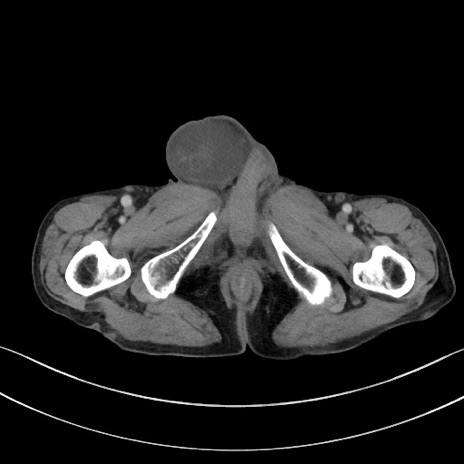

症例3(横断像)

【症例】 70歳代男性

【主訴】右鼠径部腫瘤、疼痛

【現病歴】本日朝より上記主訴あり、受診。

【既往歴】膀胱癌にて膀胱全摘、両側尿管皮膚瘻

【データ】WBC 5600、CRP 0.56